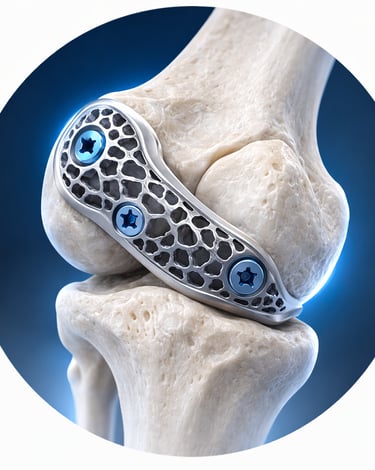

Custom-designed implants developed using advanced planning and manufacturing techniques

PATIENT-SPECIFIC IMPLANTS